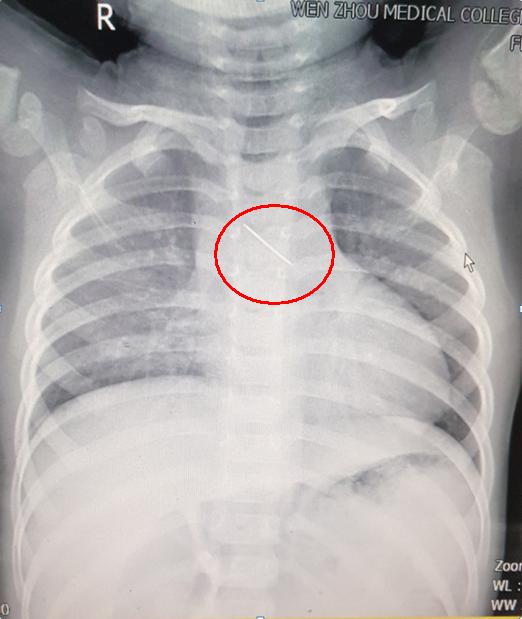

日前,温州医科大学附属第二医院急诊内科收治了这名婴儿。一枚细长的金属异物戳破婴儿气管、食管直进胸腺,贯穿主动脉。该院随即为婴儿进行开胸手术。4月11日,记者获悉,现在婴儿身体情况好转,过段时间就可出院。

结果却令人震惊。经检查发现,婴儿的胸腔内藏了一根四公分长的金属异物,已经戳破气管、食管,将近穿破主动脉,需开展手术才能取出。

吴国伟介绍,当时婴儿体内的绣花针“斜跨”在食道,贯穿主动脉和气管,前面扎着胸腺、后面抵着食道,针尖直戳主动脉。就像“羊肉串”一样,将四者串联。若通过食道取出,极有可能引起大出血。

根据图片显示,取出来的这根针有4公分长,针头有点发锈。